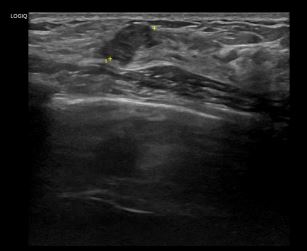

상기환자는 외부검사 이상소견으로 조직검사 권유받고  내원하신 40대 후반 여성분으로 의심스러운 우측 혹 조직검사 시행해 유방암 진단되었습니다.